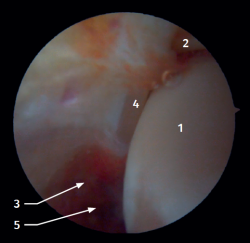

Arthroscopic anatomy of the medial complex

Arthroscopy allows us to see the deep fibers of the deltoid ligament, corresponding to the intra-articular portion of the ligament. Medial and proximal to the tip of the malleolus we have the insertion of the deep layer of the deltoid ligament. If there is no injury, we will see the anterior portion of the deep tibiotalar fibers. When injury is present, we can visualize the intermediate and posterior portion. The superficial bands, due to their more external location, are not visible by arthroscopy, unless there is no lesion of the deep bands (Figure 5).

Figure 2. Anterolateral arthroscopic view of the right ankle. 1: talar dome; 2: anterior aspect of the tibia; 3: fibula; 4: distal fibers of the anterior tibiofibular ligament; 5: anterior talofibular ligament.

Figure 3. Anterolateral arthroscopic view of a right ankle on entering the tibiotalar zone. 1: talar dome; 2: articular aspect of the tibia; 3: fibula; 4: distal tibiofibular joint; 5: distal fibers of the anterior tibiofibular ligament.